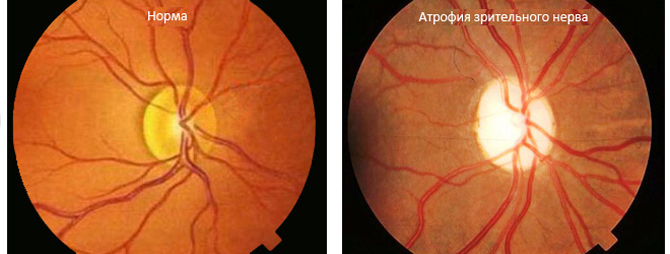

Атрофия зрительного нерва Лебера: Симптомы и лечение